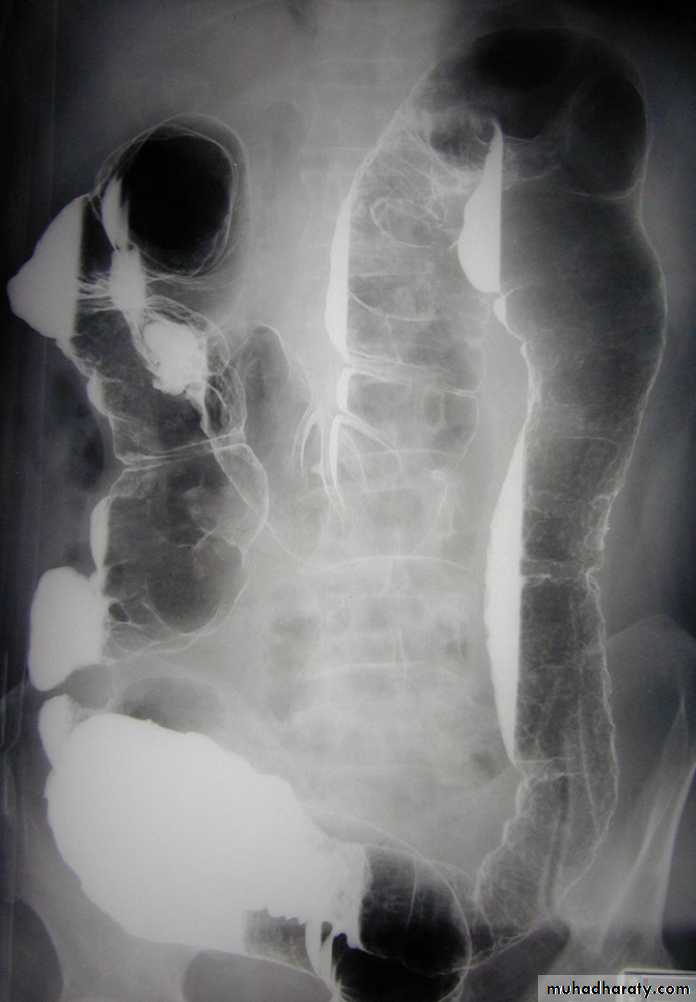

Radiological finding of CD in BA follow through :

• _Multiple mucosal ulcers aphthous ulcers.• _Transmural ulcer (Rose thorn appearance )

• _longitudinal fissures

• _Multiple skip lesions

• _when severe leads to cobblestone appearance

• _May lead to sinus tracts and fistulae

• _widely separated loops of bowel due to fibro-fatty proliferation

• _Thickened folds due to edema.

• _Pseudo diverticula formation: due to contraction at the site of ulcer with ballooning of the opposite site.

Crohns disease